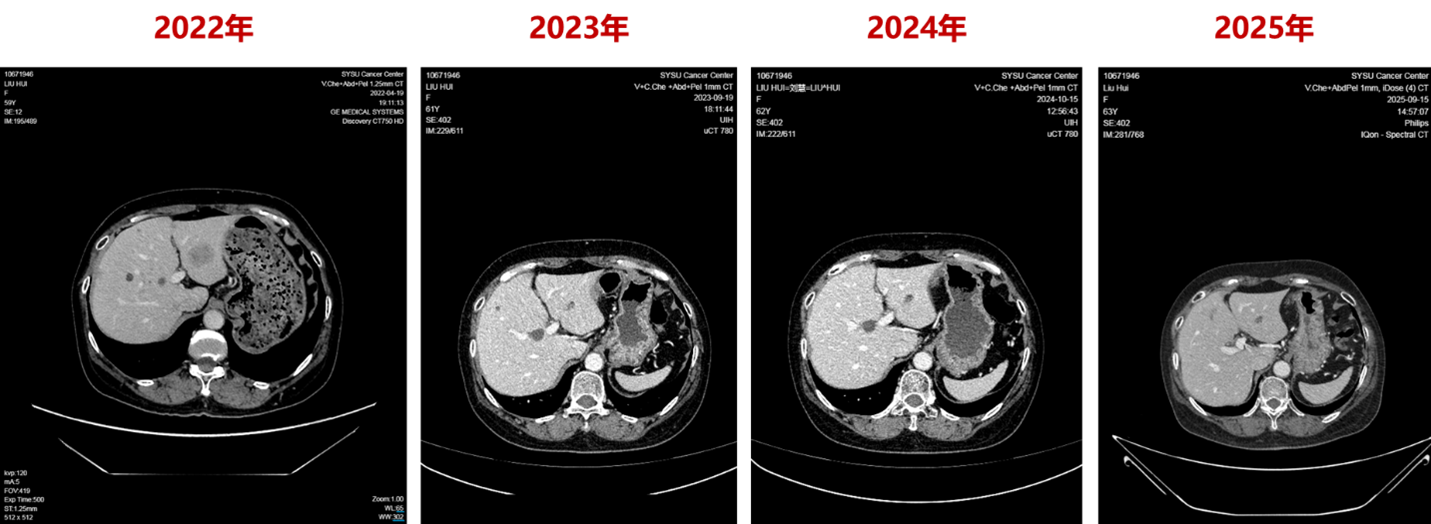

2022年4月27日,患者入组WO41554临床试验,接受“伊那利塞(GDC0077)/安慰剂+哌柏西利+氟维司群”的三靶点联合治疗。仅2个周期后(2022年6月),影像学即显示肝转移灶明显缩小;后续多次评估均维持部分缓解(PR)。

截至2025年9月,患者无进展生存期(PFS)已超过40个月,远超INAVO120研究报道的中位PFS 17.2个月。

最后,本例的PFS数据(40+月) 明显优于INAVO120研究报道的中位PFS(17.2个月)[2]。这提示在真实世界中,该方案有潜力为部分患者带来更长期的疾病控制,从而有效延缓了进入化疗的时间。鉴于INAVO120研究已证实该方案可降低33%的死亡风险并带来7个月的中位OS获益 ,我们有理由期待这位获得超长PFS的患者,将收获更积极的总生存结局。

第一,对于PIK3CA突变且内分泌耐药的患者,一线采用三联方案是实现长期疾病控制的必要策略。该患者是在辅助AI治疗后约2年半复发,属于继发性内分泌耐药 ,这与INAVO120研究入组的内分泌耐药人群特征一致 。研究数据显示,对于这类患者,双药联合治疗的疗效有限(安慰剂组mPFS仅7.3个月),而伊那利塞三联方案则将mPFS显著延长至17.2个月 。该获益在最具治疗挑战的亚组中同样显著:INAVO120研究中近80%为内脏转移患者 ,该亚组的mPFS同样被延长(13.8个月 vs 7.2个月,HR=0.51)。更重要的是,该方案将中位至首次后续化疗的时间从12.6个月大幅延长至35.6个月 ,化疗风险降低57% 。这说明在PIK3CA突变及内分泌耐药的双重压力下,三药联合是实现有效疾病控制的必需策略。